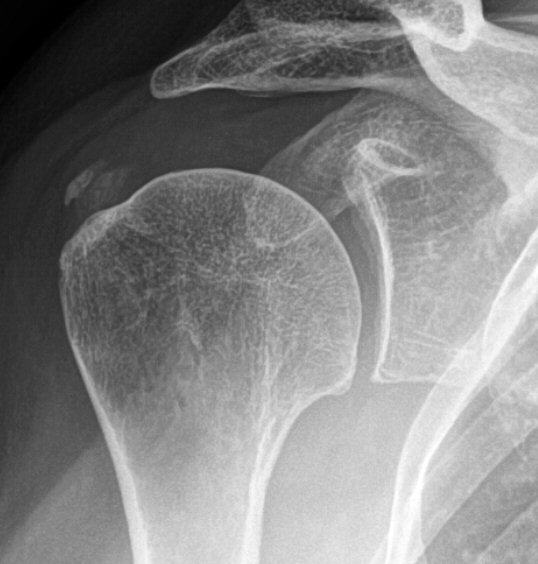

- Röntgenbild med typisk förkalkning i supraspinatussenan

Två exempel på kalkaxlar, både med kraftig smärta och förhöjt CRP men återställda efter några dagar.